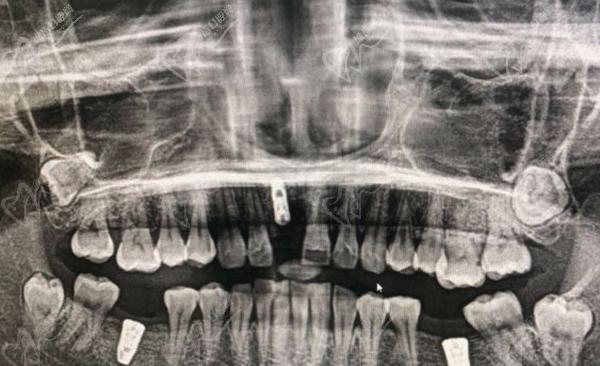

1、3D数字化导板种植术即刻种植术

上海松丰齿科蒋勇军院长擅长使用3D数字技术进行种植牙,一般是通过详细的口腔扫描和数字模型,定位患者牙槽骨的解剖结构。然后他就可以能够进行个性化的种植计划,根据患者的口腔情况和需求,为每位患者设计合适的植体位置和角度。

3d数字化种植牙图片

ps:上海松丰齿科蒋勇军院长由于熟练掌握即刻种植技术,他能够在患者同一次就诊中完成牙槽骨准备、植体植入以及修复工作。这不仅缩短了治疗周期,也为患者提供了更便捷的就医体验。

3D数字化导板种植术即刻种植术过程图